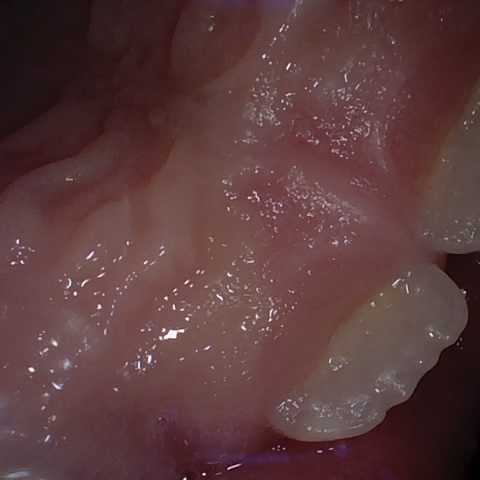

Annotated as "Good"

Original Image Rendering Image